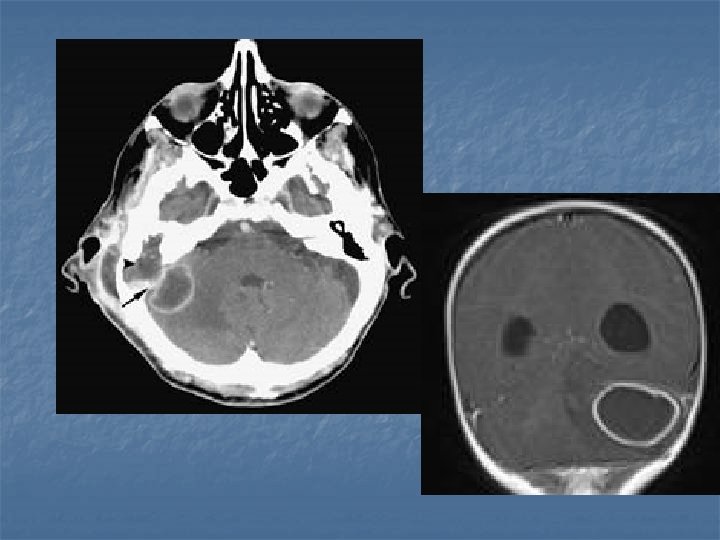

Tüberkülomlar n n İntrensek beyin kitleleri CPA’da, sellar bölgede, kavernöz sinüste, durada da tüberkülomlar tanımlanmıştır. BT’de her türlü lezyonu taklit edebilir. Genellikle izodens kitlelerdir. Çevresel veya homojen kontrast tutarlar. MR’da ise T 1’de hipo veya izointens olup kontrasttan sonra çok iyi boyanırlar. Çok sayıda, yaygın, küçük lezyonlar olarak veya matür tüberkülomlar şeklinde, daha büyük, ortası nekrotik hipointens, çevresi ödemli lezyonlar şeklinde karşımıza çıkabilirler.